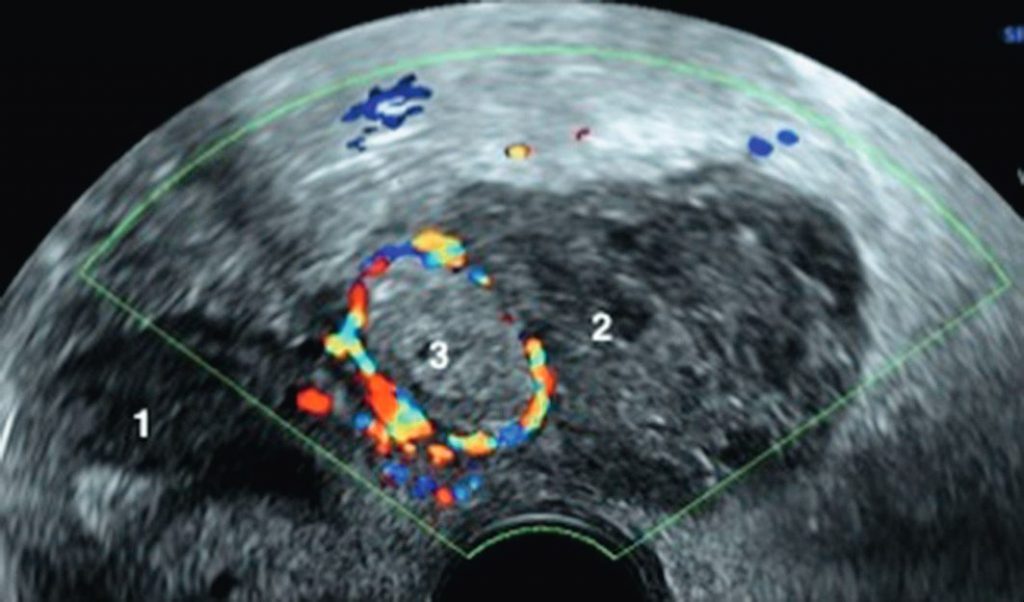

Fig. 20.1 Coupe axiale d’échographie pelvienne, chez une femme de 26 ans, présentant des douleurs pelviennes gauches, β-hCG à 1 800 UI.

1. Utérus. 2. Ovaire gauche. 3. Grossesse extra-utérine (latéro-utérine gauche) avec vascularisation périphérique au doppler couleur.

Source : CERF, CNEBMN, 2022.